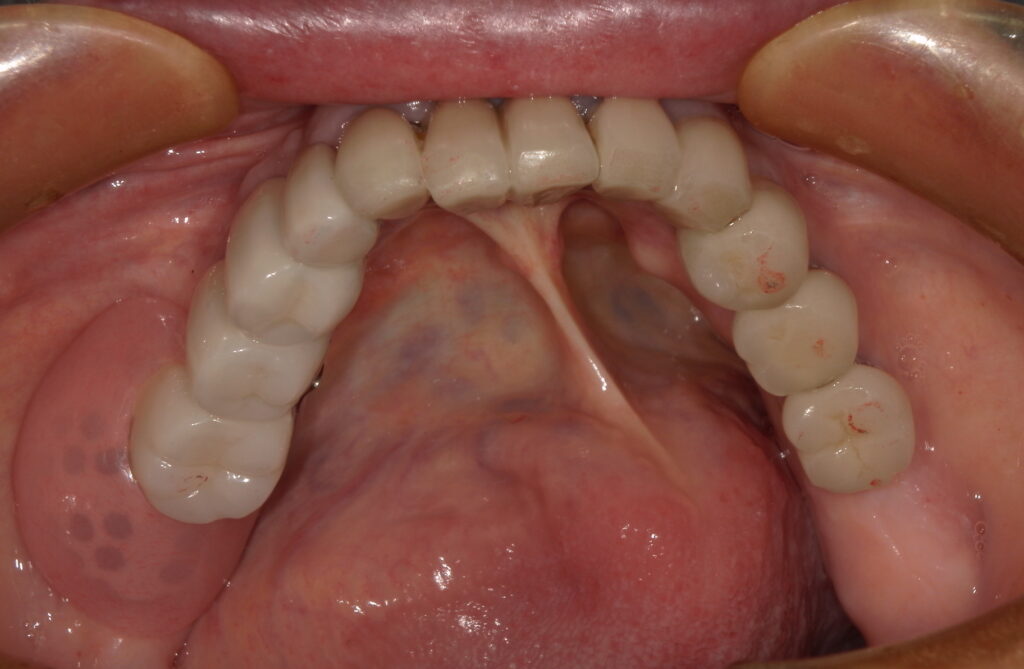

お口の中を拝見すると、上顎には前歯が3本残っていましたが、**無口蓋義歯(上あごの口蓋を覆わないタイプ)**を使用されていました。

下あごには、インプラントが数本入っておりましたが、臼歯の部分は骨が薄く、入れる事ができなかったという事でした。

• 上顎:レジリエンツテレスコープ

• 下顎:既存のインプラントを活かしたリーゲルテレスコープ

上下で状態が異なるため、それぞれに最適な方法を選択しています。

完成した上顎の入れ歯は、口蓋をしっかり覆う設計ですが、空気が入らず、安定感のある仕上がりに。

下顎は、これまで小臼歯までしか噛めなかった状態から、奥歯までしっかり噛めるように。